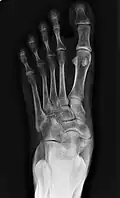

-

From left to right: Type 1, 2 and 3 -